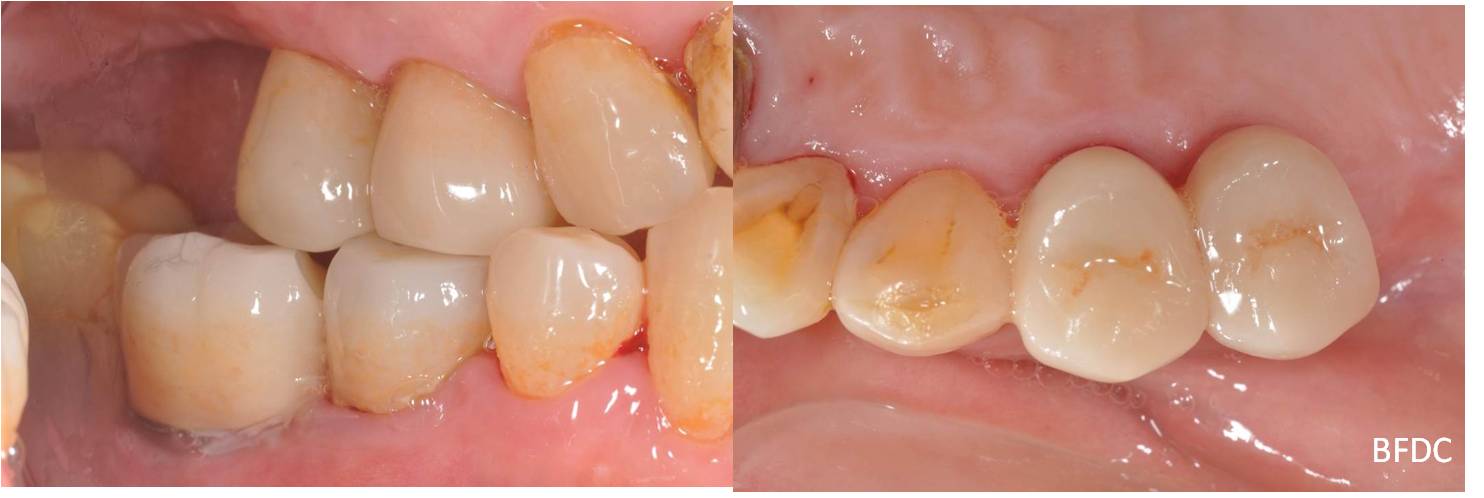

治療前,牙齦下蛀牙,牙齒動搖

術前、術後比較